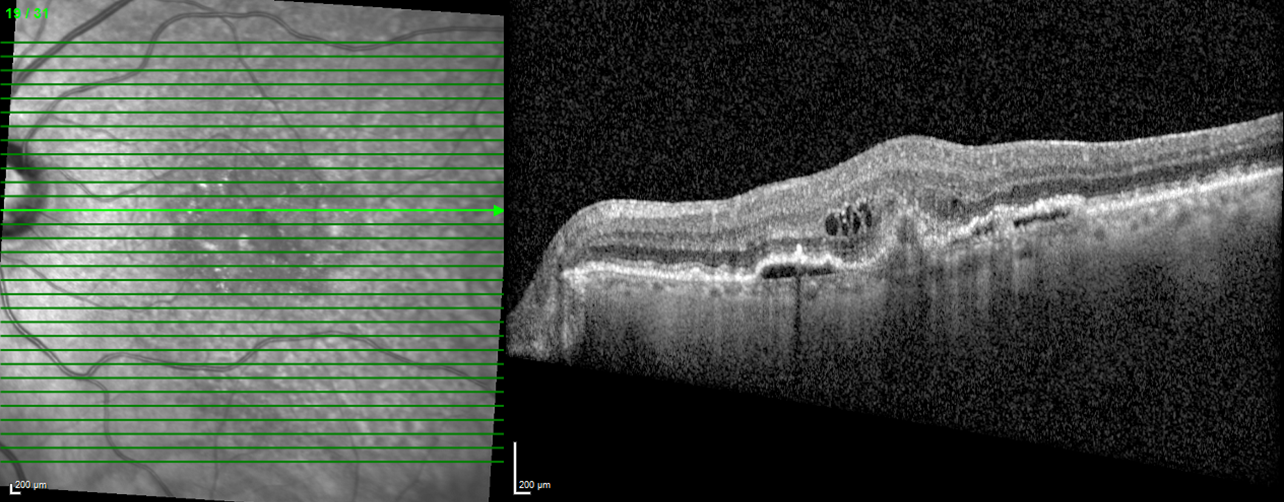

The picture below shows the left macula of a patient with Age-Related Macular Degeneration (ARMD). The photo on the left is how the macula appears when the doctor examines the eye - the optic nerve is on the left edge - the macula is in the central part of the photo. The green line represents the specific area of the macula that is being examined. The corresponding image on the right is the cross sectional view of the retina. One can see irregular thickness and elevations in the center part of the photo. On part 2 of this blog, I will give more information on how to look at an OCT.